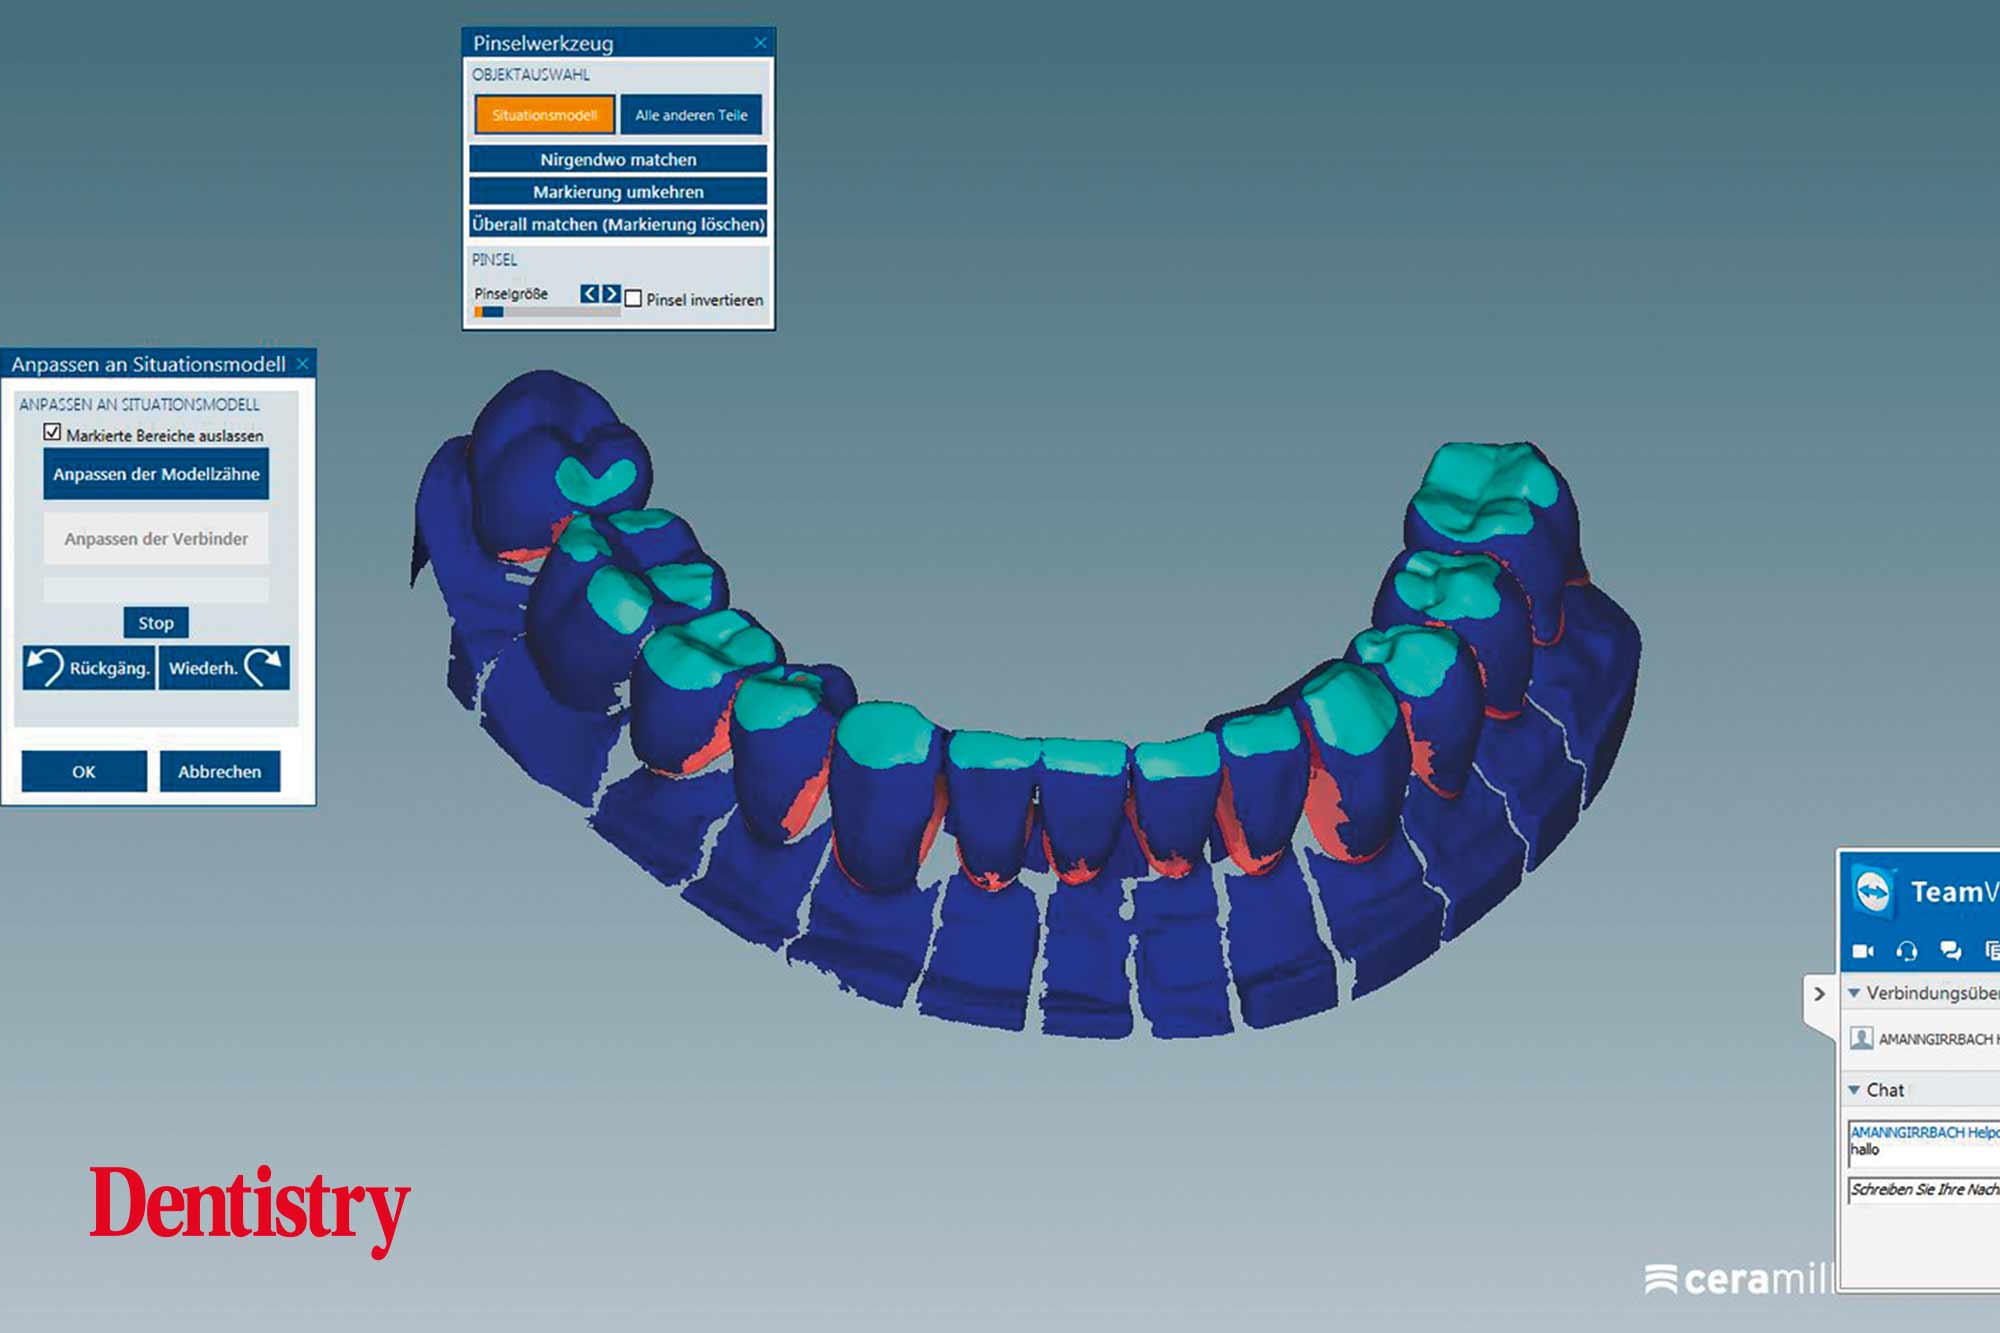

Using the CAD software (Figure 12), we were able to round off and refine the areas on the temporary crowns that had been ground and modified intraorally. As a result, this left the remaining areas unchanged.

Figure 13 shows the areas that were adjusted intraorally in green and the remaining unchanged areas in blue. The plan was to fabricate Ceramill Zolid FX crowns on the maxillary teeth first. This is so subsequent corrections on the lower temporary crowns would mean that less corrections would be necessary for the final lower crowns.